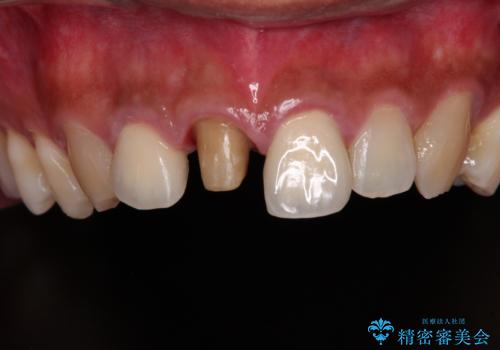

時間の経過とともに、セラミックにしなかった当該歯の変色が目立つようになり、オールセラミッククラウンにて補綴することとしました。

変色した歯はきれいになり、両隣の歯とも自然に馴染み、ご家族からも好評で大変満足されました。